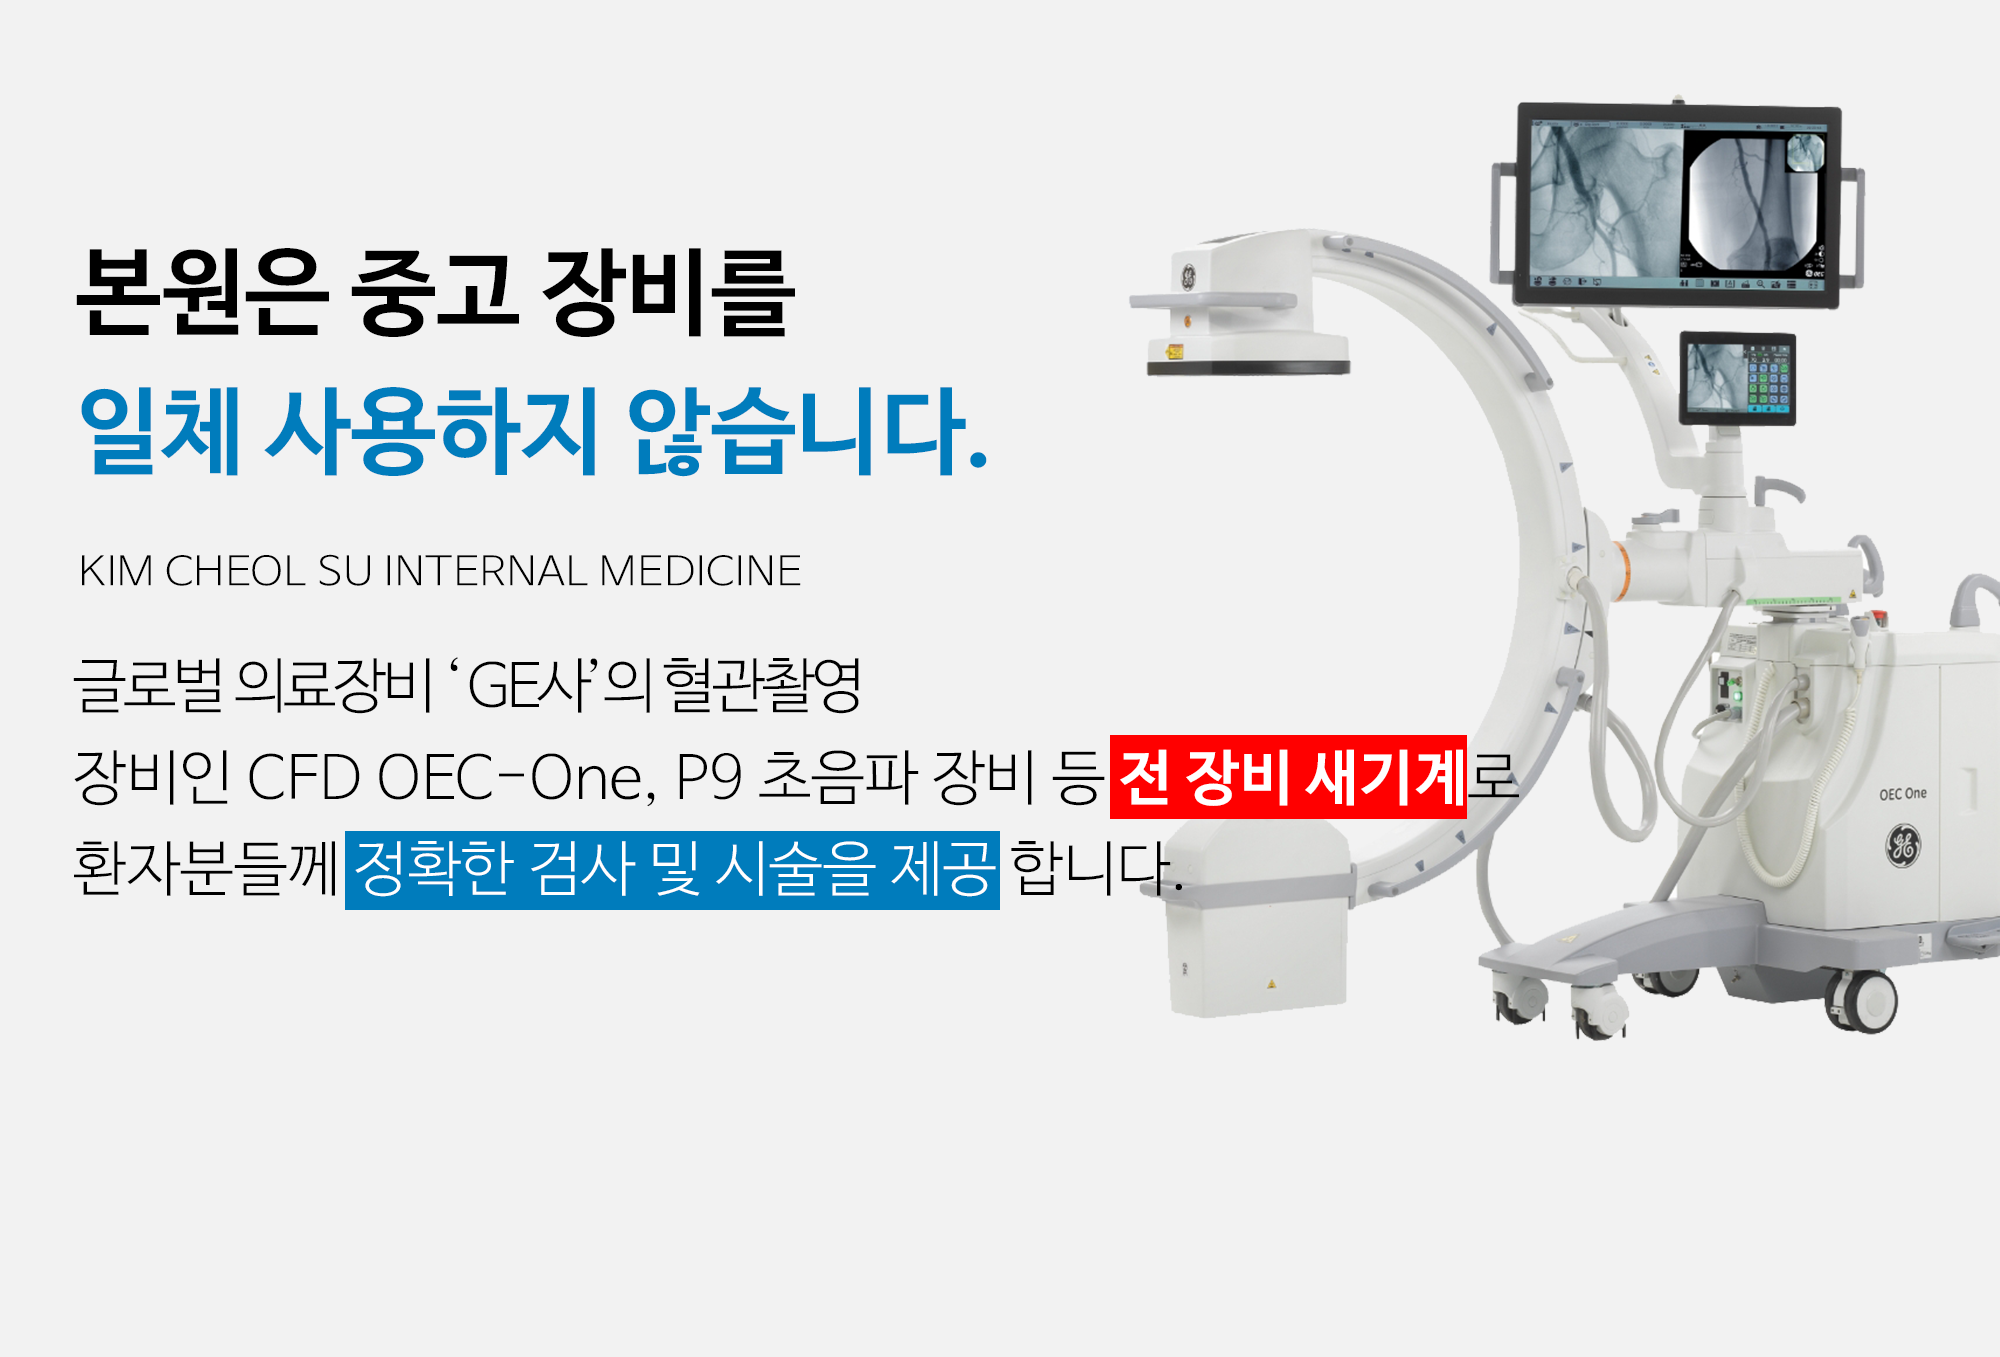

보유장비소개

본원은 성능과 안전성이 검증된 의료 장비를 엄선하여 사용합니다.